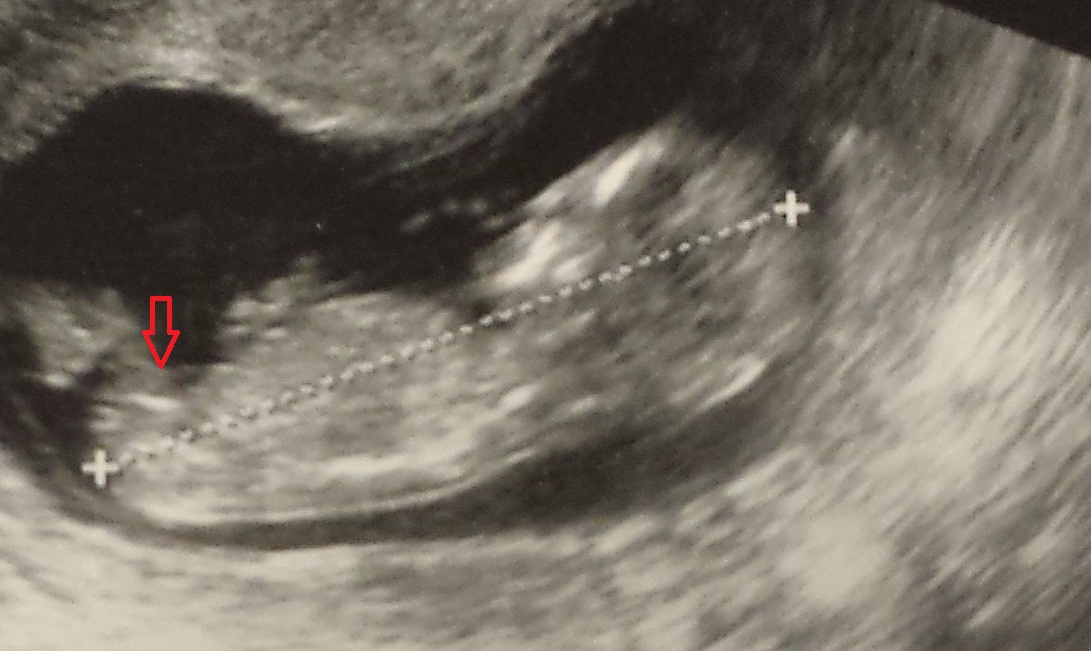

12 weeks and 2 days...i have attached a pic with an arrow thinking thats the nub...Attachment 19161